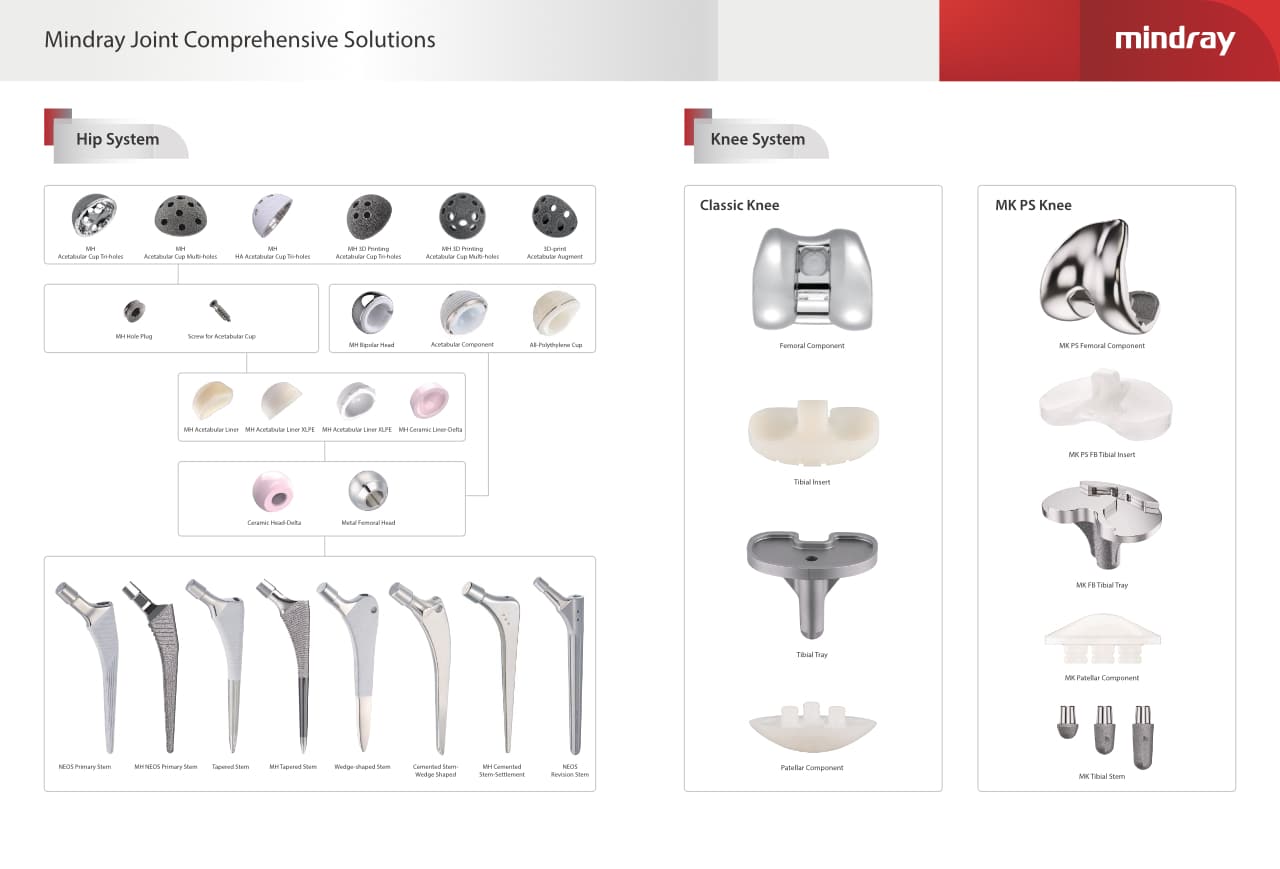

–Ъ–Њ–Љ–њ–ї–µ–Ї—Б–љ—Л–µ —А–µ—И–µ–љ–Є—П –і–ї—П –∞—А—В—А–Њ–њ–ї–∞—Б—В–Є–Ї–Є

–С–µ–і—А–Њ

–Ъ–Њ–Љ–њ–Њ–љ–µ–љ—В—Л –≤–µ—А—В–ї—Г–ґ–љ–Њ–є –≤–њ–∞–і–Є–љ—Л MH

–Т–Ї–ї–∞–і—Л—И–Є

–С–µ–і—А–µ–љ–љ—Л–µ –≥–Њ–ї–Њ–≤–Ї–Є

–С–µ–і—А–µ–љ–љ—Л–µ –љ–Њ–ґ–Ї–Є

–Я—А–Є–љ–∞–і–ї–µ–ґ–љ–Њ—Б—В–Є